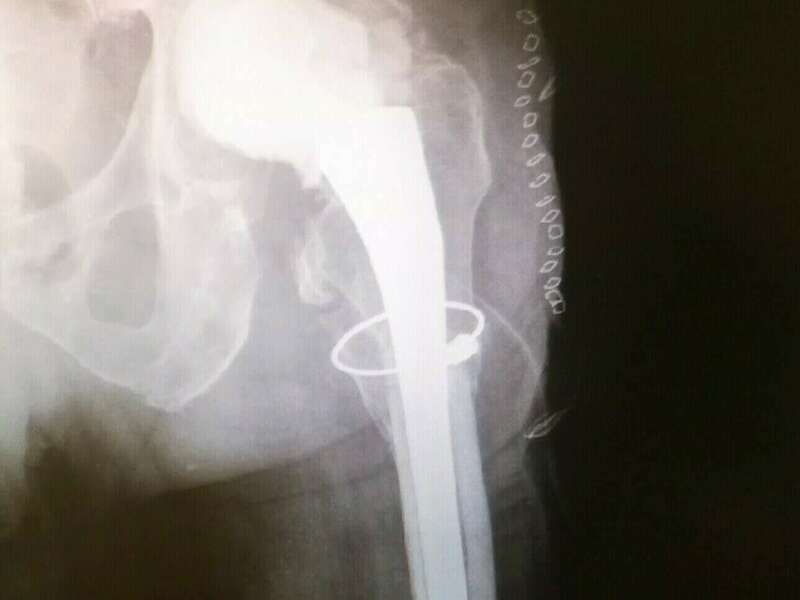

En cas d’infection tardive, la prise en charge varie d’une région à l’autre. Nous optons pour la solution en deux temps. Le premier temps correspond au retrait de l’ensemble des implants, à la réalisation de prélèvements microbiologiques, et à la mise en place d’un Spacer au ciment aux antibiotiques. Selon les constatations per-opératoires, le chirurgien décidera ou non d’introduire une antibiothérapie probabiliste avant d’avoir les résultats bactériologiques.